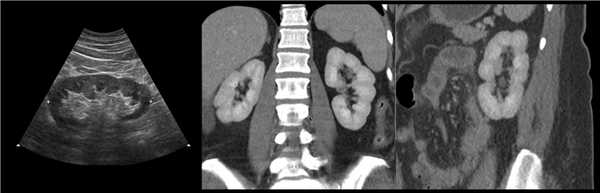

Рисунок. На УЗИ (1) и КТ (2, 3) контур почек волнистый. У эмбриона почка развивается из отдельных долек, которые сливаются по мере их роста. Дольчатое строение почек хорошо видно у плода и новорожденных, в единичных случаях сохраняется у взрослых.

Рисунок. На УЗИ округлое образование разделяет почечный синус на два сегмента с общей лоханкой; междолевые артерии огибают образование; эхогенность и интенсивность сосудистого рисунка внутри близка корковой зоне. Заключение: Гипертрофия колонны Бертини или неполная паренхиматозная перемычка. Это вариант нормального строения почки. Термин «неполное удвоение ЧЛК» неверный, т.к. неполная паренхиматозная перемычка не является признаком удвоения ЧЛК.

Рисунок. На УЗИ синус почки разделяет полная паренхиматозная перемычка (1, 2). В таких случаях разграничить удвоение почки от гипертрофии колонны Бертини поможет экскреторная урография. Удвоенная почка покрыта общей фиброзной капсулой. Полное удвоение предполагает наличие двух лоханок, двух мочеточников и двух сосудистых пучков. Неполноудвоенная почка (3) питается одним сосудистым пучком, мочеточник может быть удвоен вверху и впадать в мочевой пузырь одним или двумя устьями. Удвоение ЧЛК и мочеточников — фактор риска развития патологии (пиелонефрита, гидронефроза и др.).